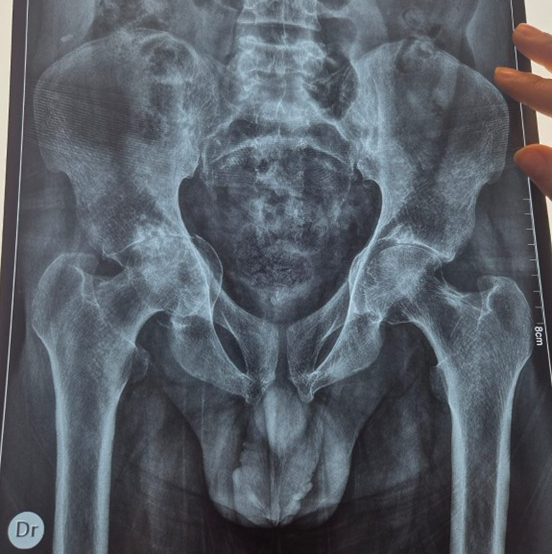

La radiographie du bassin montre des remaniements osseux diffus, bilatéraux et symétriques, intéressant les ailes iliaques, les régions péri-acétabulaires et les branches ischio-pubiennes. On note un épaississement cortical, une condensation osseuse hétérogène et une trabéculation grossière, avec un respect relatif des interlignes coxofémoraux. Le bilan biologique montre habituellement une élévation des phosphatases alcalines totales, reflet de l’hyperactivité ostéoblastique. La scintigraphie osseuse permet de préciser l’extension des lésions et met en évidence une hyperfixation intense et localisée.

L’ensemble des données cliniques et radiographiques est en faveur d’une maladie de Paget osseuse, à prédominance pelvienne (explications ci-dessous).

Devant des remaniements osseux pelviens diffus, bilatéraux et hétérogènes chez un sujet d’âge mûr, la maladie de Paget doit être systématiquement évoquée afin d’éviter un diagnostic erroné de spondyloarthrite ou d’arthrose.